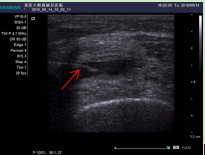

图二(箭头指向已进入积液中的针尖)